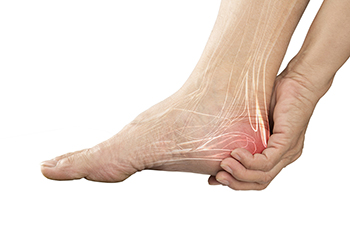

Exercise is another key aspect of arthritic foot care. Exercise not only strengthens and stretches your muscles and joints, but helps to prevent further injury and pain as well. Stretching the Achilles tendon, the tendon located in the back of your heel, will give you added mobility and reduce pain due to stress. Another thing you can do is massage your feet, kneading the ball of your foot as well as your toes from top to bottom.

Stretching the Achilles tendon is a simple exercise that you can do at home anytime. Lean against the wall with your palms flat against the surface while placing one foot forward, towards the wall, and one foot behind you. Bend your forward knee towards the wall while keeping your back knee locked straight, and make sure both your heels are completely touching the ground at all times. This will stretch your Achilles tendon and calf muscles as well. You will feel the stretch almost immediately. You can also stretch your toes in a couple ways. One involves taking a rubber band and wrapping it around both your big toes while your heels remain together. Then, pull them apart to stretch your big toe. You can also place a rubber band around all the toes of one of your feet. Then, try to separate each individual toe, stretching them all.